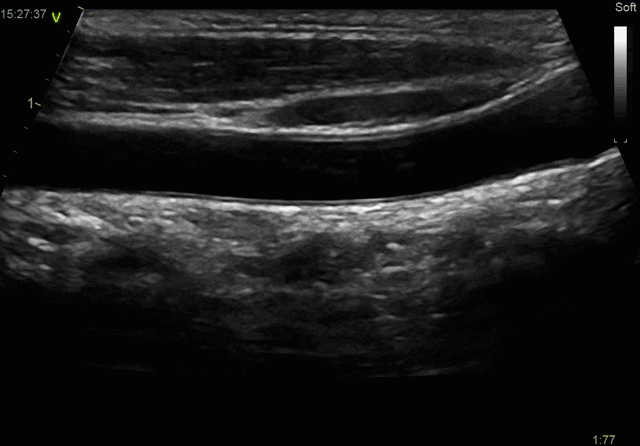

- Ангиология

- Близко расположенные органы и поверхностные структуры

- Скелетно-мышечная система